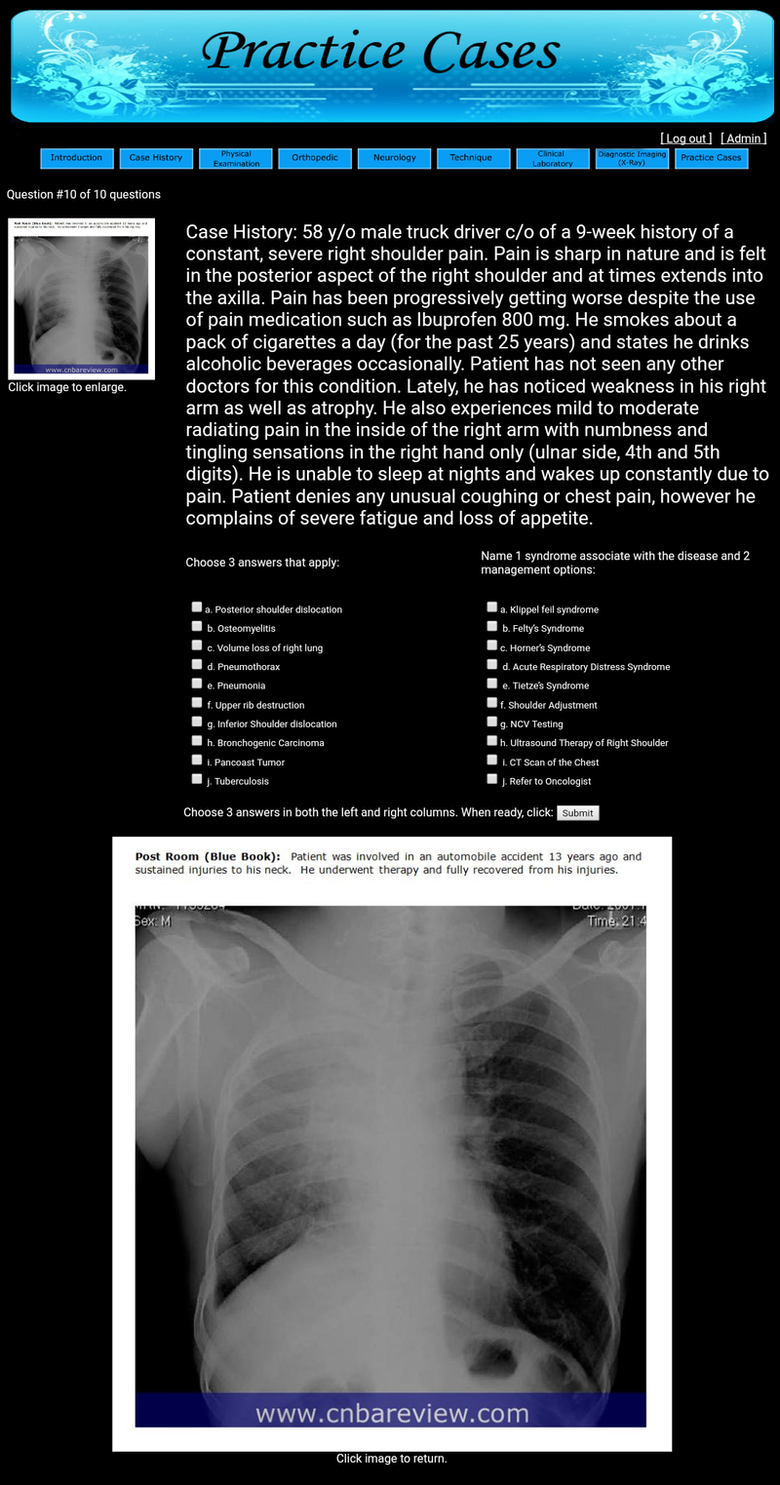

4. Post Room/Blue

Book/Booklet: The CNBA Review Practice Cases will

contain a section called: Post Room or Blue Book or Booklet

similar to the ones presented during the post station rooms of

the NBCE Examination -- In this section additional information

regarding the patient is provided. As you finish examining the

patient in the pre-station room (during the NBCE Examination)

and are tansferred to the post station room to answer the

questions, you will be provided with a booklet, which will

contain additional information regarding the patient. Make sure

to glance over this section and apply it if needed (it usually

contains important and useful information).